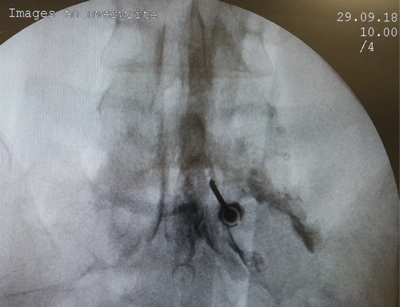

Figura 1